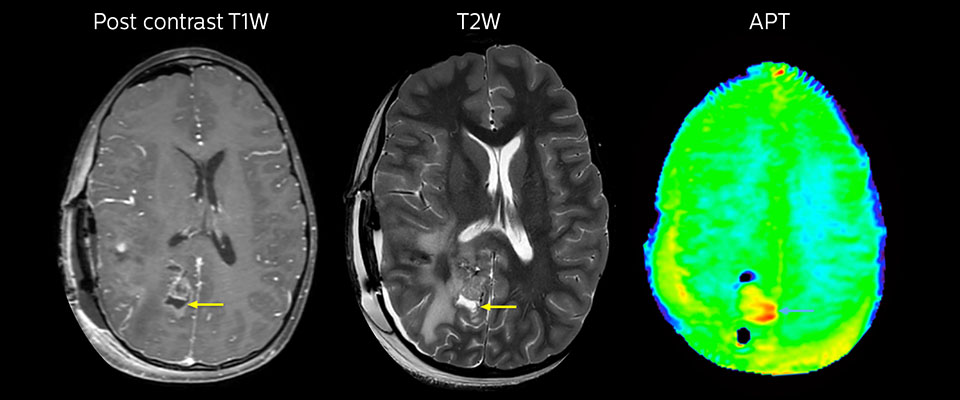

MRI may be performed after tumor resection, to look for residual tumor or tumor regrowth. Also here, the different contrast mechanism of APT may help in diagnosis. Dr. Miller remembers a particular case.

“After a very good resection, we saw small changes on the postcontrast T1-weighted and the T2-weighted images that looked like a post-surgical little bit of fluid. Interestingly, however, we saw a focal area of APT signal, right in the center of that abnormality. As we usually do when a bit unsure, we followed it up and, unfortunately, found tumor regrowth in that region,” Dr. Miller says. “Cases like this motivate me, and others who care about this population, to investigate how this APT method could be used on large scale in this population and help us in providing high value diagnostic information.”

The hospital’s physicians also saw a case where APT had a negative predictive value. Following the resection of a highgrade tumor, they saw a similar small change in the images of this patient. However in this case, the APT signal was rather low. In a recent rescanning of this patient, no recurrence was seen.